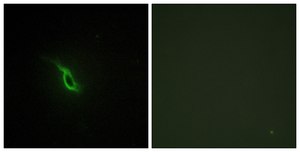

ELISA: 1:20000, immunofluorescence: 1:100-1:500, immunohistochemistry: 1:50-1:100, western blot: 1:500-1:1000